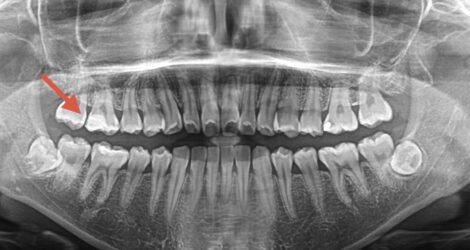

こんにちは歯科助手の毛利です! 今回はE-Maxインレーの症例をご紹介します🦷 ☆50代女性 ☆プラスチックの下に2時虫歯 ☆クリーニングで虫歯が見つかり処置 ☆右上6 治療の動画↓ https://youtu.be/J30HyLbj5sQ 🦷費用🦷 E-Maxアンレー ¥88,000×2 処置時間 ①形成、光学 …